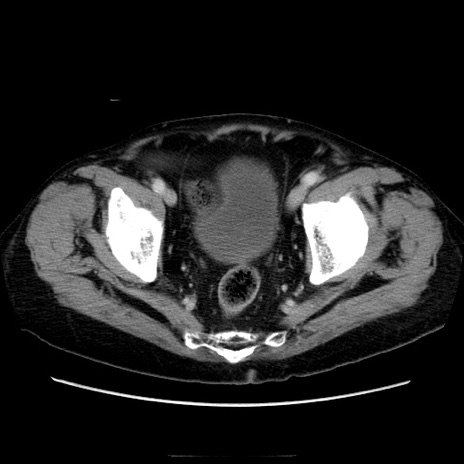

冠状断像

【症例】70歳代男性

【主訴】腹痛

【現病歴】肝硬変・肝細胞癌にてかかりつけの方。約9時間前に食後より腹痛出現。症状が徐々に増悪し、嘔吐出現したため来院。

【既往歴】肝硬変、肝細胞癌(RFA、TACE後)

【身体所見】意識清明、表情苦悶様、BT 36℃、BP 129/78mmHg、P 88bpm、SpO2 97%(RA)、右上腹部から心窩部にかけて圧痛あり、反跳痛なし、筋性防御あり。

【データ】WBC 5800、CRP 0.16